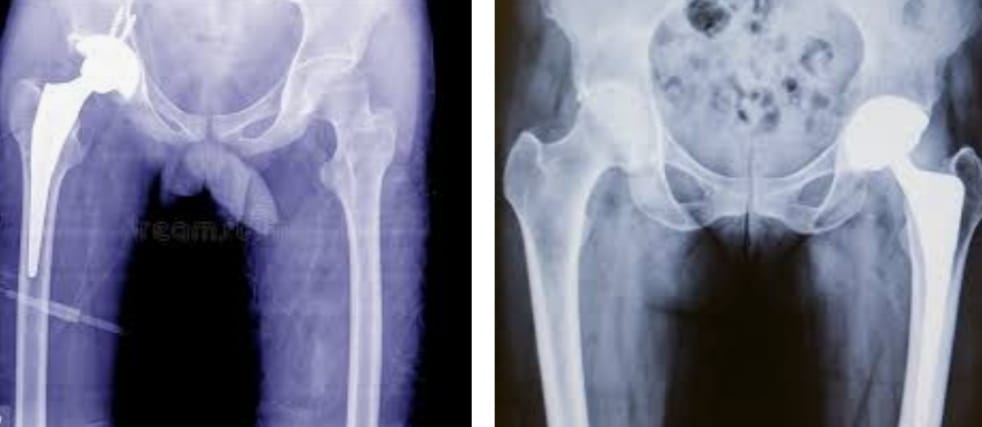

The Veer Hospital provides effective and high-quality healthcare services with 20+ departments, 16 special units and 50+ physicians. We offer an up-to-date medical approach in an ethical and reliable environment. We maintain our reputation in the health sector with our experienced medical staff who continuously improve qualified healthcare with an uncompromising focus when it comes to proficiency and academic values.